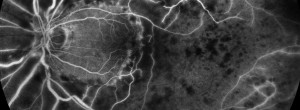

Retinal vein occlusions.

The Brighter Study: a 24-month, phase IIIB, open-label, randomized, active controlled, three-arm, multicenter study assessing the efficacy and safety of an individualized, stabilization criteria-driven pro re nata dosing regimen with 0.5-mg ranibizumab intravitreal injections applied as monotherapy or with adjunctive laser photocoagulation in comparison to laser photocoagulation in patients with visual impairment due to macular edema secondary to branch retinal vein occlusion (BRVO)

The Crystal Study: a 24-month, phase IIIB, open-label, single arm, multicenter study assessing the efficacy and safety of an individualized, stabilization criteria-driven pro re nata dosing regimen with 0.5-mg ranibizumab intravitreal injections applied as monotherapy in patients with visual impairment due to macular edema secondary to central retinal vein occlusion (CRVO)